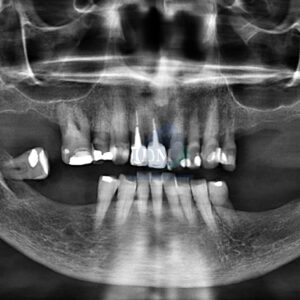

Paciente masculino de 50 años acude al Instituto de Diagnóstico Maxilofacial con el motivo de consulta de una tomografía de haz cónico de campo reducido